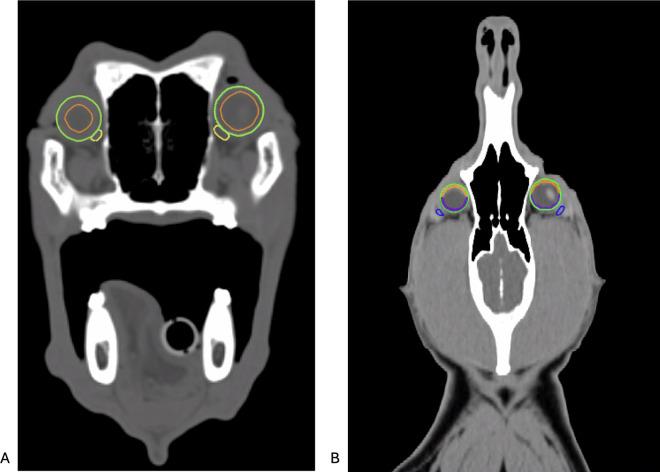

Acute toxicity and survival were documented in dogs undergoing radiotherapy for sinonasal tumors. However, few studies specifically investigated ocular toxicity, resulting in limited data on radiation tolerance thresholds. This study aimed to quantify acute ocular toxicity, compare toxicity levels using three different scoring systems, and establish practical preliminary dose-response limits. Dogs with sinonasal tumors treated with a definitive-intent 10-fraction radiotherapy protocol were included if they underwent prospective ophthalmic examinations, both prior to radiotherapy and at least once within three months following treatment. Ocular toxicity was assessed using three scoring systems: 1) Modified McDonald-Shadduck (evaluated by ophthalmologists), 2) Veterinary Radiation Therapy Oncology Group (VRTOG) 1.0 (evaluated by radiation oncologists), and 3) VRTOG2.0 (evaluated retrospectively). Radiation doses to each eye, retina, cornea, lacrimal, and accessory lacrimal gland were documented, and adherence to the new institutional ocular dose constraints was analyzed. Seventy client-owned dogs (140 eyes) were enrolled between 2016 and 2024, yielding 241 ophthalmic examinations. Clinically relevant ocular toxicity was identified in 28 eyes (20%) according to the modified McDonald-Shadduck system, 14 eyes (10%) using the VRTOG1.0 system (grade ≥2), and in 15 eyes (11%) using VRTOG2.0 toxicity (grade ≥3). Adherence to our institutional constraints resulted in low rates of clinically relevant toxicity: only 0.7% of eyes according to VRTOG 1.0 and 1.4% according to VRTOG2.0. TD5% and TD50% risk thresholds were established to facilitate optimized planning and reduced ocular risks. In conclusion, all dogs showed rather mild and only rarely clinically relevant ocular toxicity. Clinically relevant results of the very detailed modified McDonald-Shadduck scoring system seem to be accurately reflected by the VRTOG2.0 scoring system, which is more practical for daily clinical assessments. Detailed ocular evaluations are recommended primarily for dogs with clinically relevant VRTOG2.0 toxicity. Adherence to institutional ocular dose constraints significantly minimizes the risk of clinically relevant ocular toxicity.